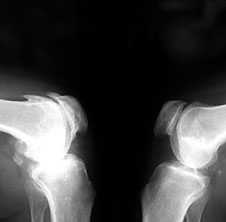

3. Заострение краев суставных поверхностей мыщелков бедренной и большеберцовой кости, чаще в медиальном отделе сустава (связано с большей нагрузкой на этот отдел сустава), особенно при наличии варусной деформации сустава; реже – в латеральной части или одновременно в обеих половинах суставной поверхности (рис. 2).

Рис. 2. Rо-графия коленных суставов в боковой проекции.

Артроз феморопателлярных суставов (больше слева). Артроз коленных суставов (I ст по Kollgren справа, IV ст. по Kollgren слева)

При прогрессировании артроза коленных суставов (соответствует 3–4 стадиям артроза по Kellgren):